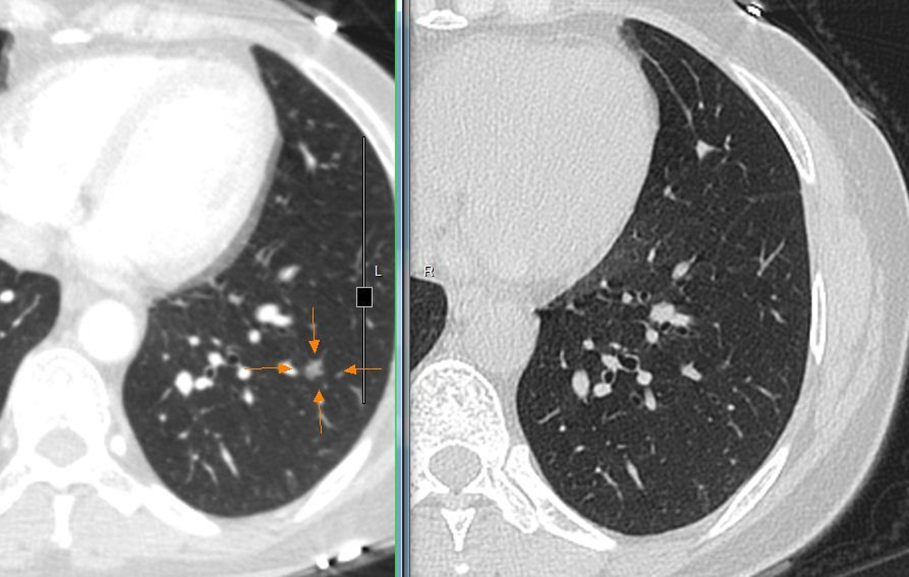

这是我前一段时间在门诊碰到的一名患者,经过门诊治疗后肺部结节消失了。